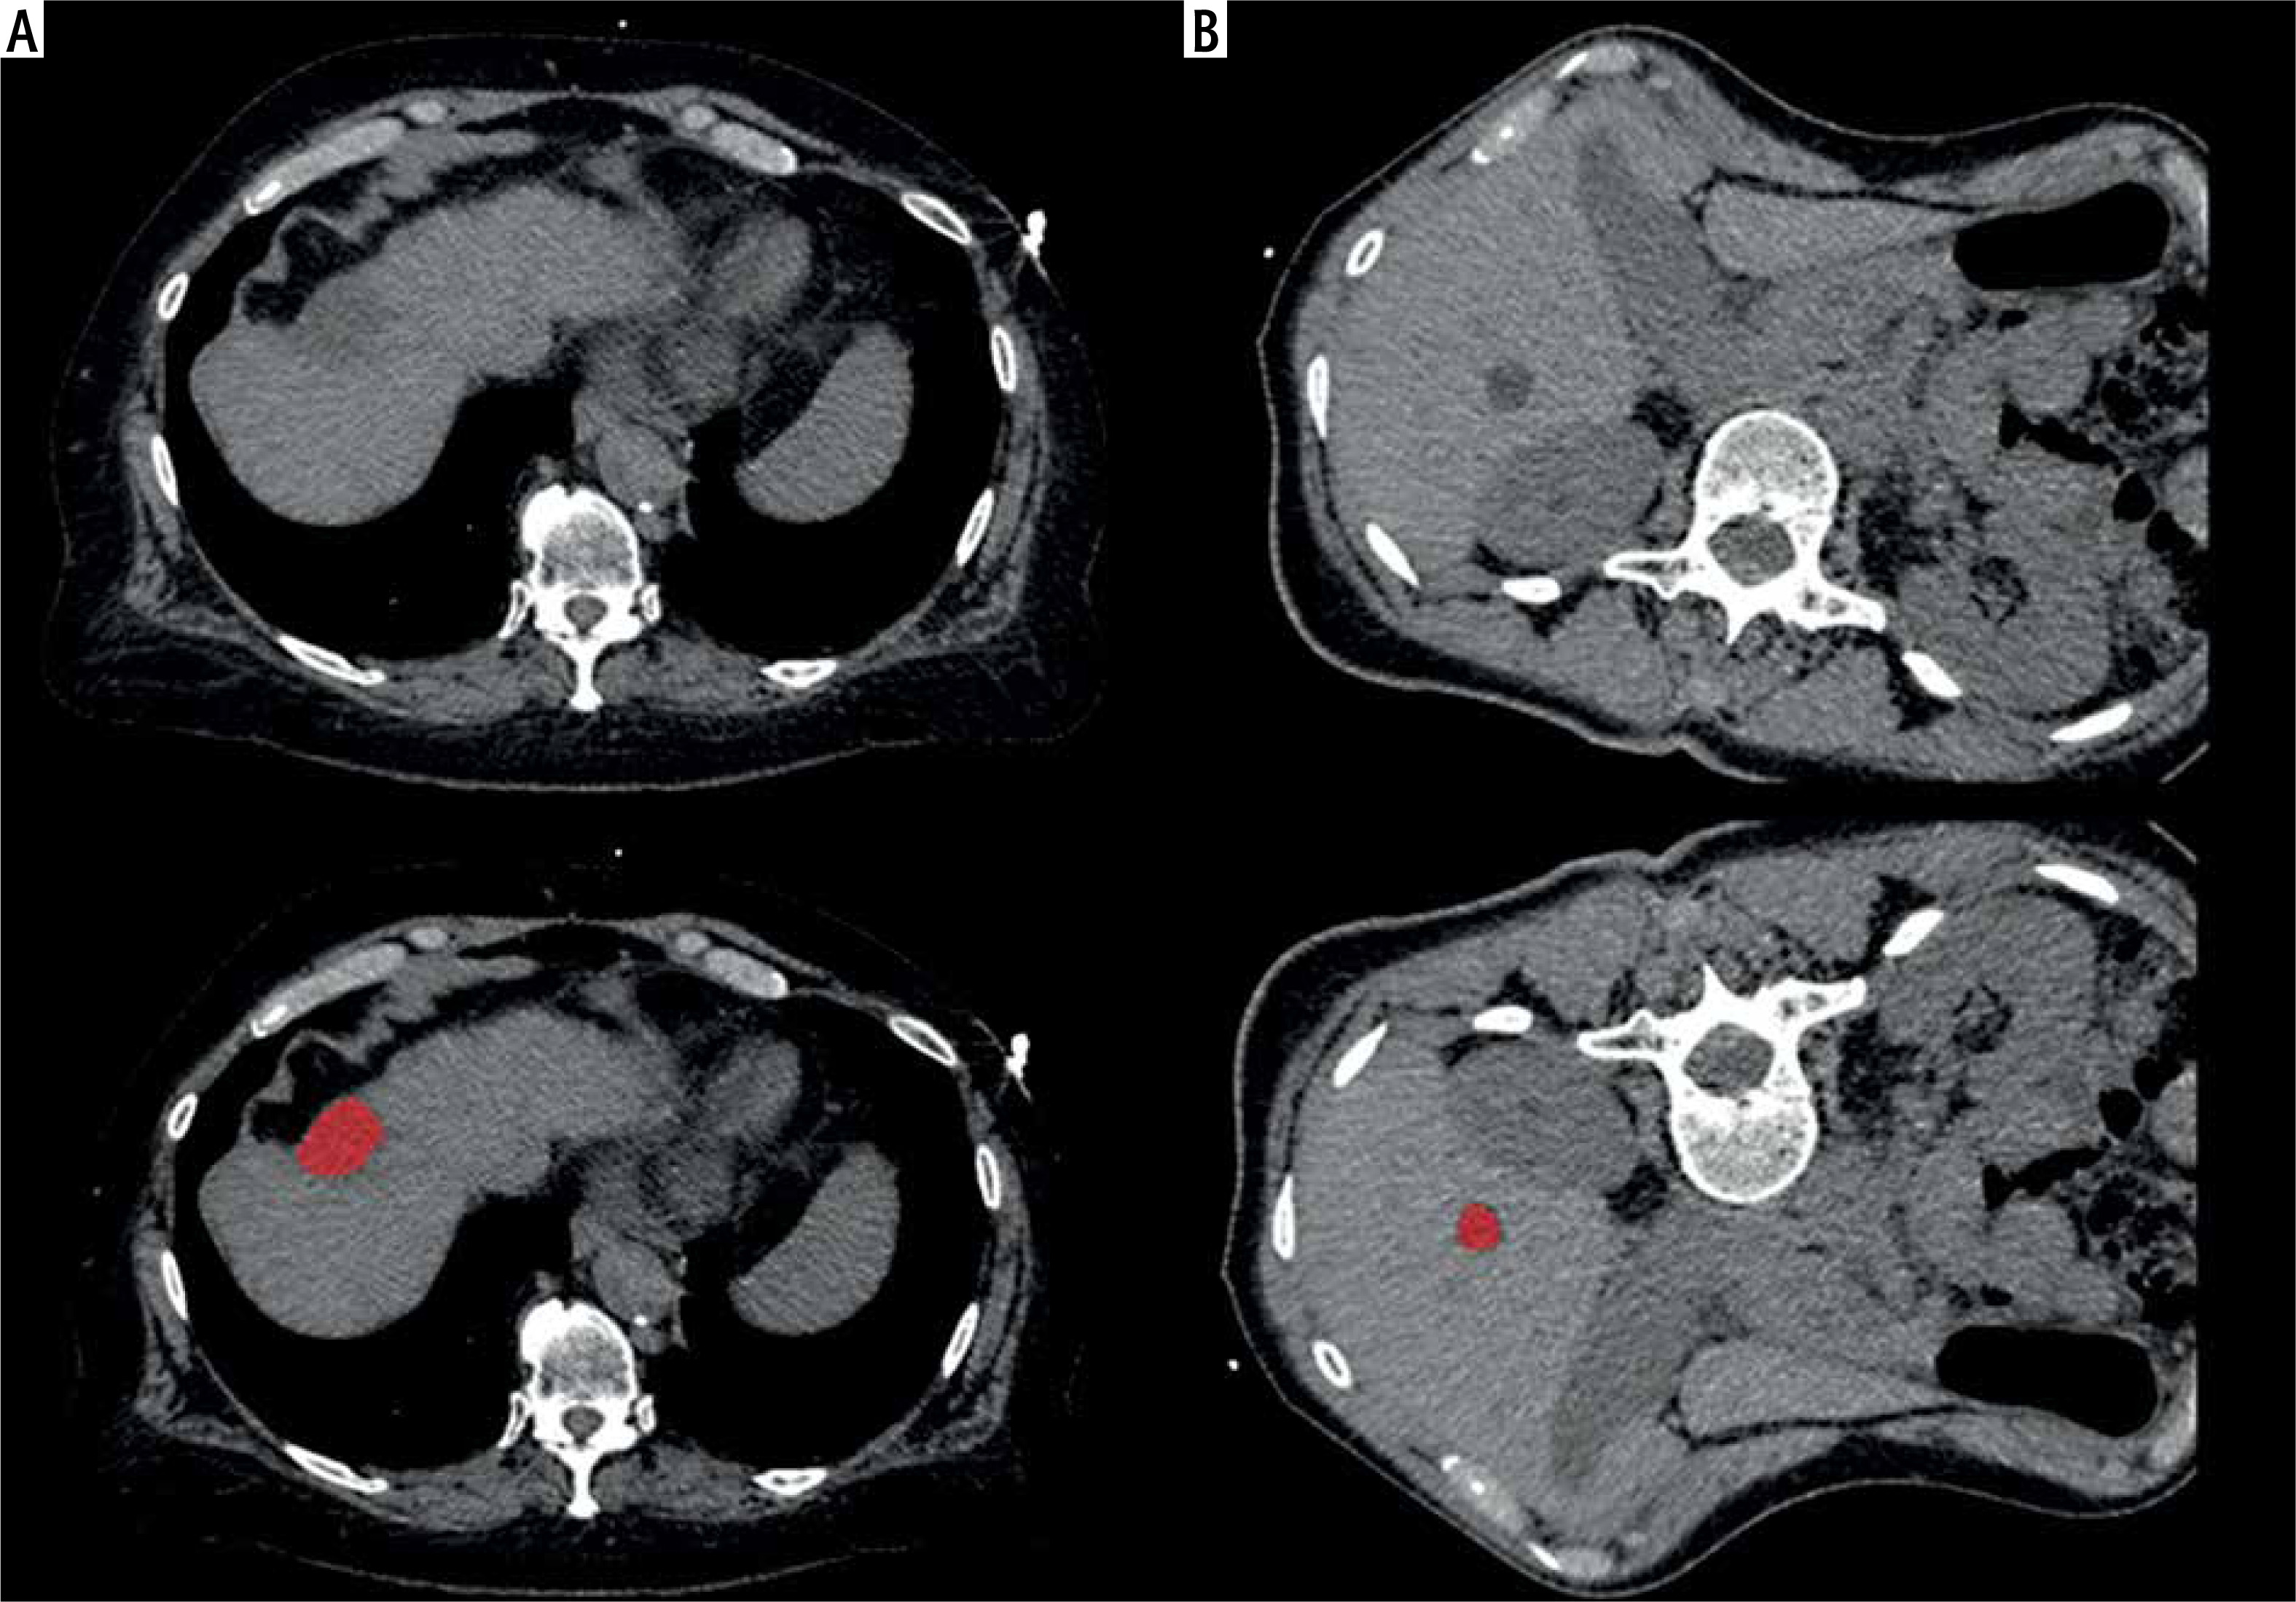

Computed tomography images were further analyzed with the dedicated software MaZda (version 4.7, available at http://www.eletel.p.lodz.pl/mazda/) [19, 20]. A region of interest (ROI) was drawn on the largest slice of the target lesion. The ROI was drawn within the liver lesion with 2 mm distance to the adjacent parenchyma. Texture analysis measurements were blindly taken for the bioptic and clinical results. For each ROI, gray-level (µ) normalization was utilized to µ ±3 standard deviations to reduce the influence of contrast and brightness variation on the texture features, as performed previously [16, 17]. Texture features of various groups were extracted for each patient including histogram parameters, second order texture features of different groups comprising co-occurrence matrix run-length matrix, absolute gradient, autoregressive model (theta 1 to 4, sigma), and wavelet transform features. Altogether, 279 texture features were calculated in all lesions. Two representative cases of the patient sample are shown in Figure 1 with the drawn ROI.

Fig. 1

Representative cases of the patient sample. A) 68-year-old female patient, no steatosis, no fibrosis, diagnostic biopsy with benign result, platelet count 316,000/μl, distance to liver capsule 0 mm, no hemorrhage. B) 61-year-old female patient, steatosis degree 5%, minimal fibrosis, non-diagnostic biopsy, platelet count 81,000/μl, distance to liver capsule 13 mm, no hemorrhage